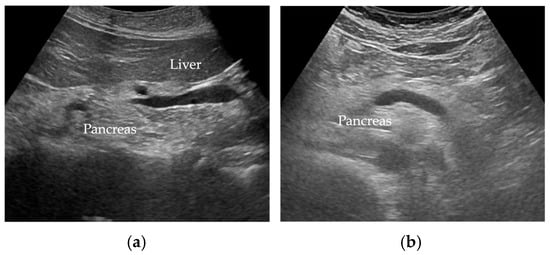

Wang et al. [35] reported FP was diagnosed when there was an increase in echogenicity of the pancreatic body over that of the kidney. Because the pancreas often could not be directly compared with the kidney within the same imaging window (Figure 2), the examiner assessed the differences between hepatic and renal echogenicity, and between hepatic and pancreatic echogenicity, to obtain an objective pancreatorenal echo contrast [35]. In another study, pancreatic echogenicity was compared to the liver echogenicity at the same depth on a longitudinal scan taken near the abdominal midline [36]. Figure 2 shows ultrasonographic images of a non-fatty pancreas and a fatty pancreas.

Figure 2.

Ultrasonographic images show (a) a non-fatty pancreas with normal echogenicity and (b) a fatty pancreas with increased echogenicity of the pancreatic body.